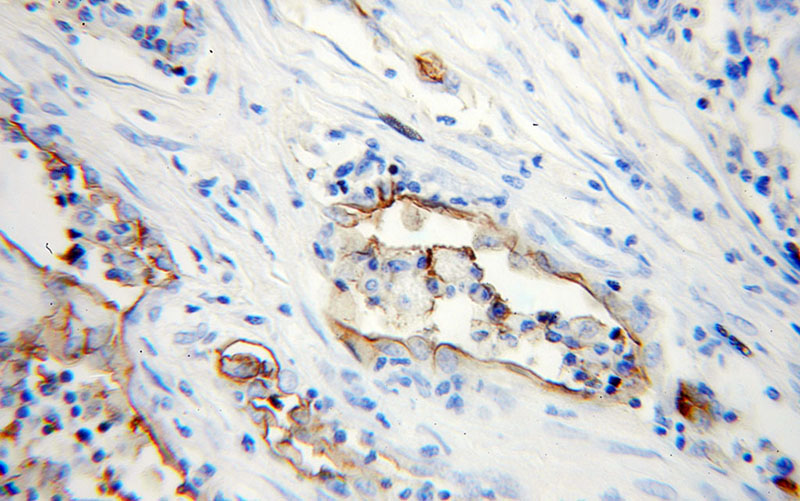

Immunohistochemical of paraffin-embedded human lung cancer using Catalog No:111587(ICAM-1 antibody) at dilution of 1:50 (under 25x lens)